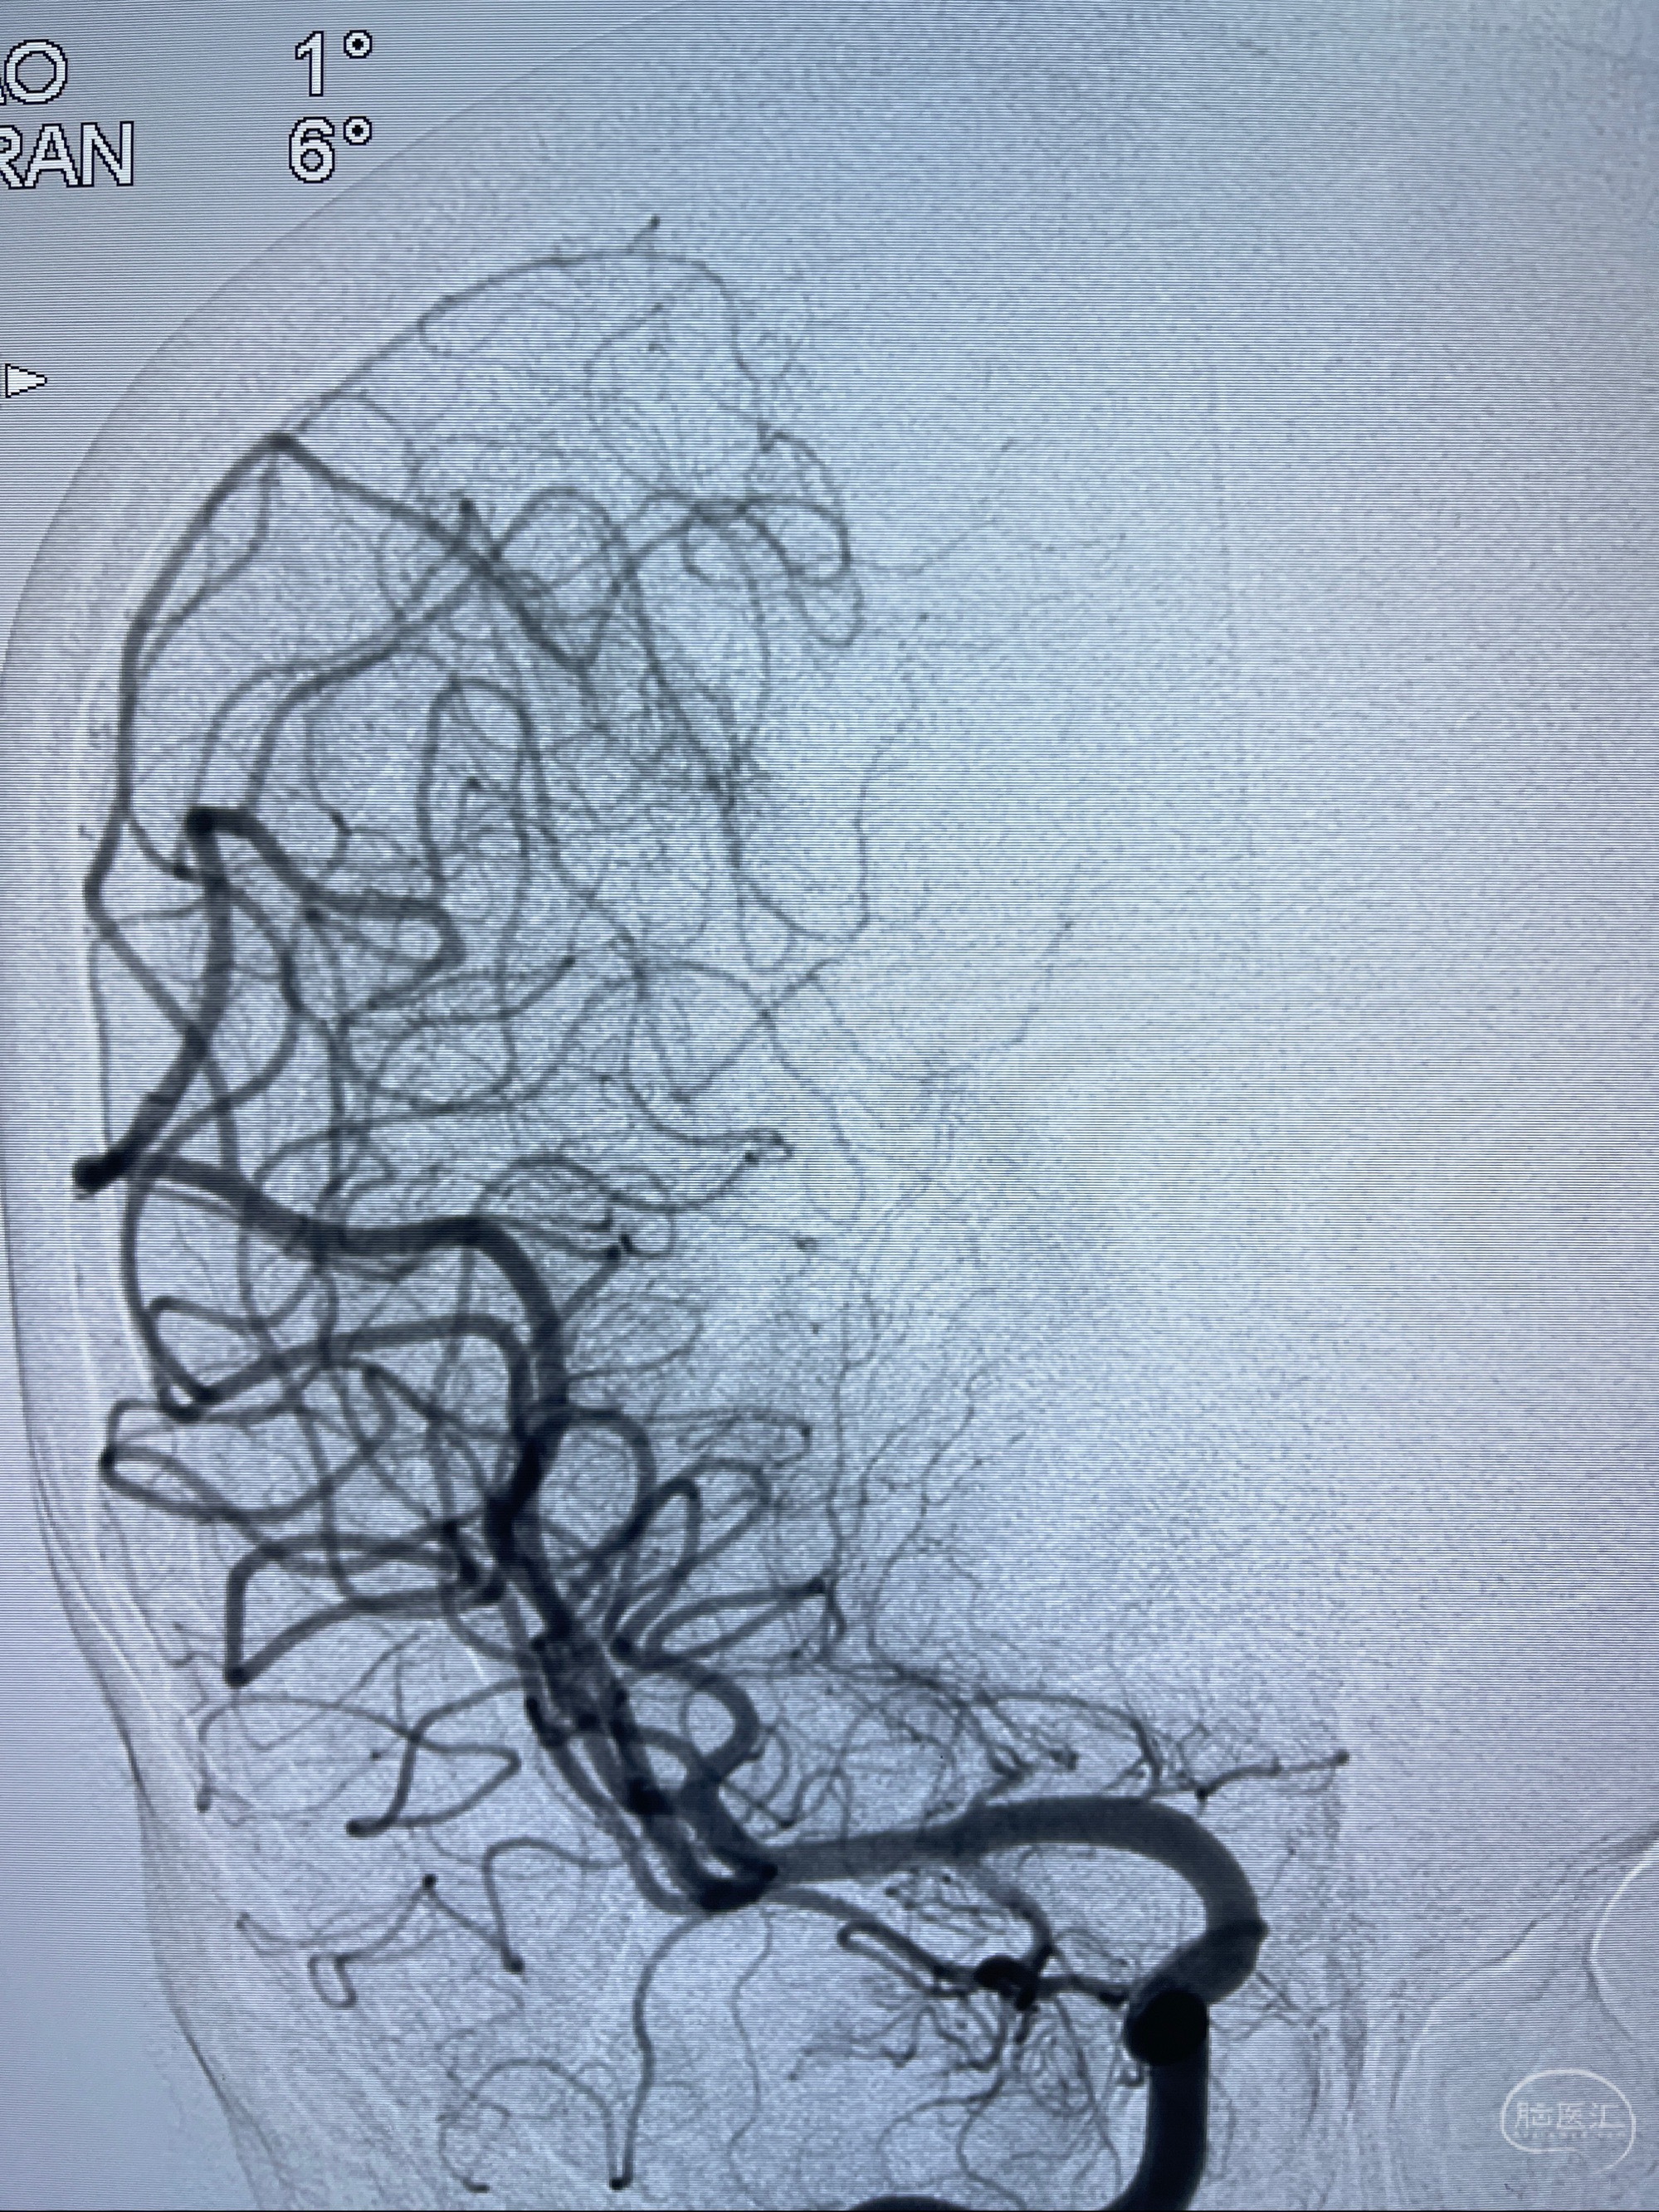

2023-08-14DSA:

左侧大脑中动脉动脉瘤,约2.6-2.8-3.4-2mm大小(瘤颈部、瘤体部、瘤高)